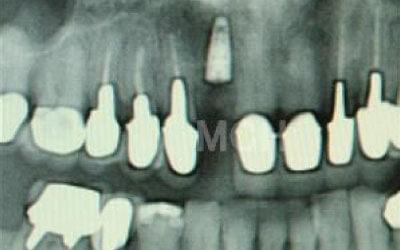

歯が抜けた後の治療について、多くの方が悩まれています。

特に、抜けたのが前歯ですとなおさら気になりますよね。 今回のご質問ですが、抜けた部分の骨が薄いなどの理由で「インプラントはできない」と言われた可能性があります。

前歯はもともと骨が薄く、歯が抜けると時間の経過とともにさらに骨が痩せてきてしまうので、インプラント治療の難易度が高い場所です。 ただ結論からお話すると、インプラント治療は可能です。

なぜなら、もし仮に骨が薄くても、骨の治療によって厚みが増せば、安全にインプラント治療が行えるからです。

なお、前歯のインプラント治療をご希望の方には、注意していただきたい点が4つほどあります。 1)インプラント治療を行う前に、骨の治療が必要かもしれません。

2)骨の治療から始めると、その分、治療期間が長くなります。

3)骨の治療は、通常のインプラント治療よりも難易度が高いため、経験の豊富な先生やインプラント認定医のいる歯科医院で治療を受けることをお勧めします。

4)骨の状況をしっかり把握するためにも、CT撮影が必須となります。 また、インプラント治療においては、周囲の歯の状況や咬み合わせの問題などもしっかりと考えて治療するのがとても大切です。